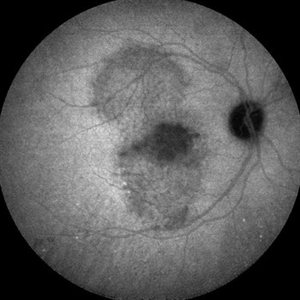

Tractional Retinal Detachment Pre-Repair

56-year-old woman with type 2 diabetes prior to tractional retinal detachment repair.

Photographer: Kenneth Thompson, Marietta Eye Clinic

Imaging device: Zeiss FF450

Condition/keywords: tractional retinal detachment, vitrectomy